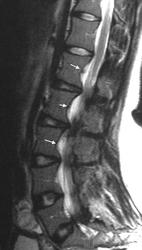

Элсберга-Дайка симптом (рентг.) - рентгенологически определяемое расширение интерпедикулярного расстояния и деформация (вогнутость) внутренних поверхностей ножек дуг. Характерен для длительно существующих объемных процессов позвоночного канала (опухоль, дермоидная киста, дермальный синус).

(С. A. Elsberg, 1871-1948, американский хирург  S. С. Dyke, совр. англ. патолог) рентгенологически определяемая деформация ножек дуг позвонков и увеличение расстояния между ножками дуг; признак опухоли спинного мозга.

При опухолях, растущих из позвоночника, и невриномах на рентгенограммах в ряде случаев обнаруживаются патологические изменения со стороны тел позвонков (остеопороз, компрессия позвонка и др.). Нередко выявляется синдром Эльсберга - Дайка, для которого характерна неправильная форма корней дужек позвонков и асимметрия расстояния между ними и остистым отростком.